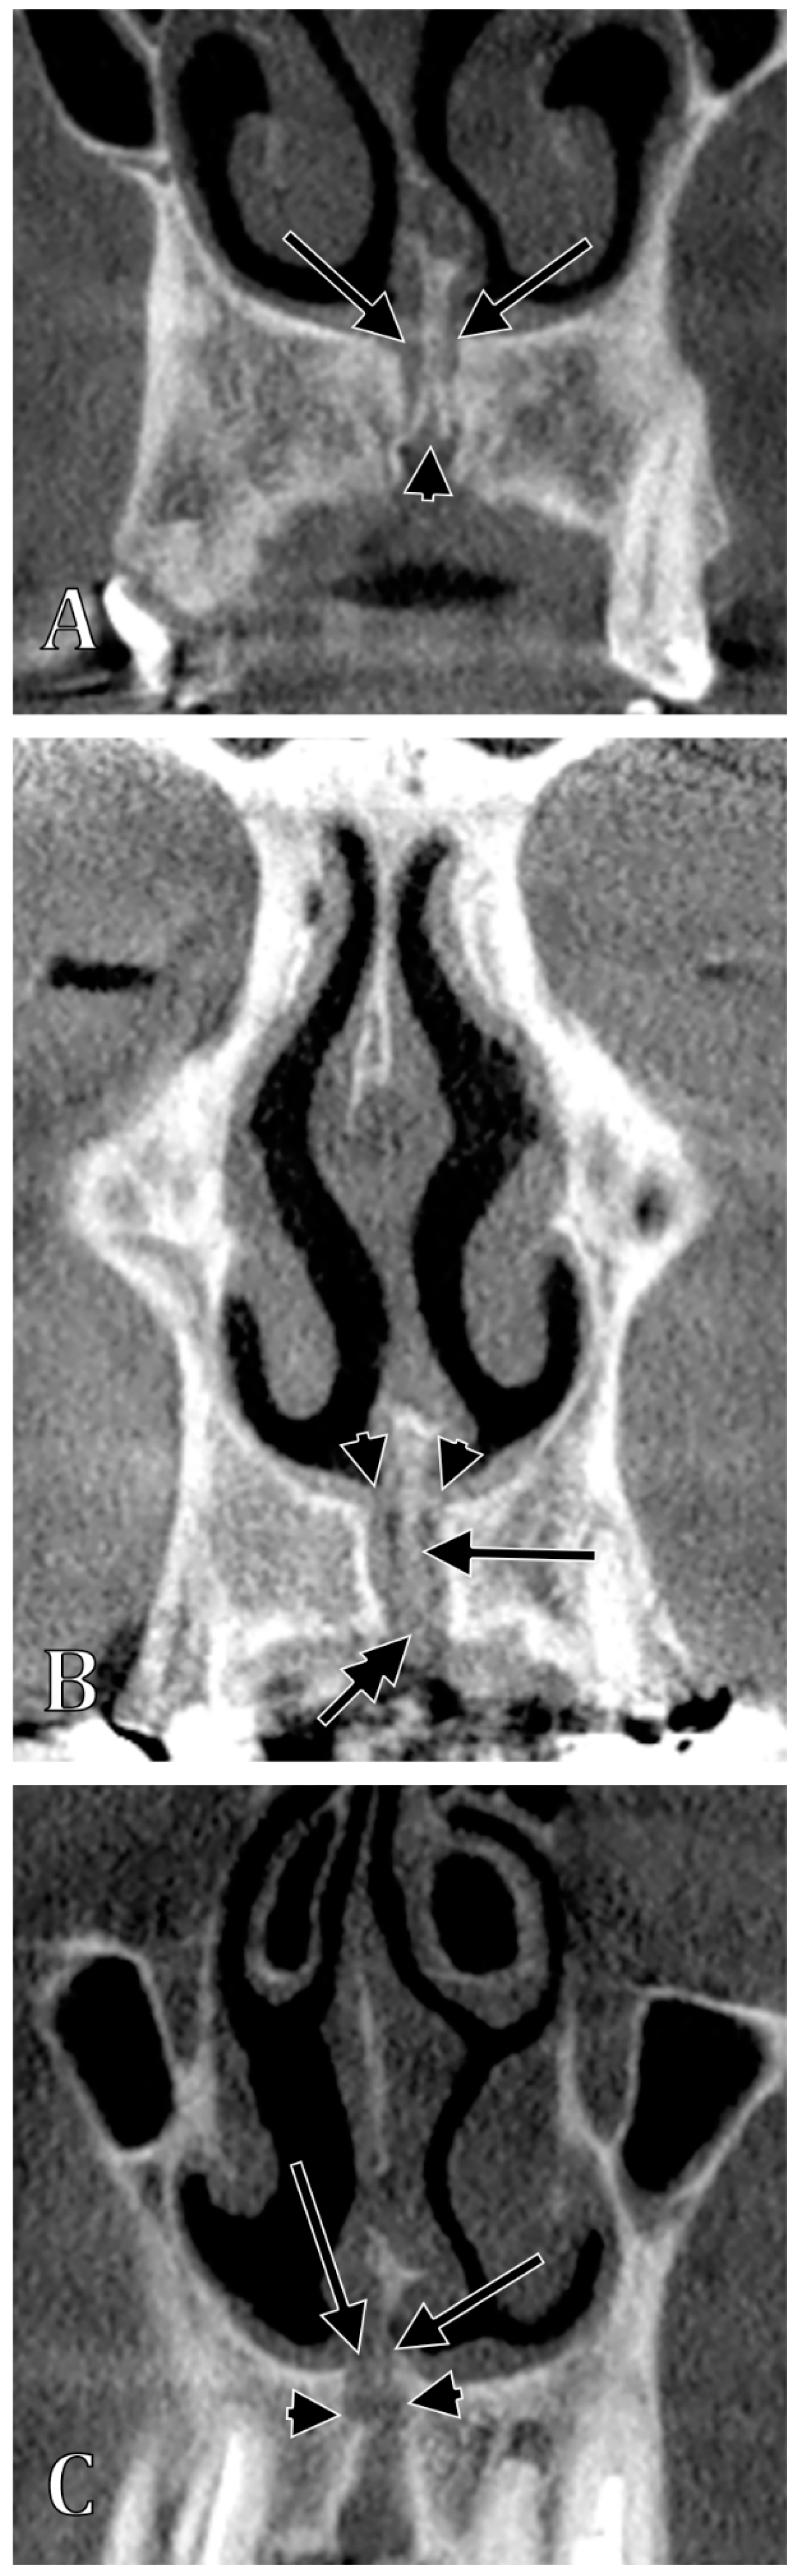

| Type of the NPC/IC | Characteristics of Types | Subtypes | Characteristics of Subtypes |

|---|---|---|---|

| I | NPC/IC present, 2 nasopalatine foramina | Ia | “Y”-shaped NPC/IC, with no secondary canaliculi |

| Ib | “Y”-shaped NPC/IC, with secondary canaliculi separated by a sagittal septum | ||

| Ic | “Y”-shaped NPC/IC, with unilateral secondary canaliculi separated by a coronal septum | ||

| Id | “Y”-shaped NPC/IC, with bilateral secondary canaliculi separated by a coronal septum | ||

| Ie | “Y”-shaped NPC/IC, with an added superiorly blind-ended median canal | ||

| If | parallel proper NPCs/ICs separated by septum | ||

| Ig | parallel proper NPCs/ICs unseparated by septum (NPC/IC unique, two nasopalatine foramina) | ||

| II | NPC/IC absent, 2 nasopalatine foramina | ||

| III | NPC/IC unique, 1 nasopalatine foramen | IIIa | unique median nasopalatine foramen, inferior to the nasomaxillary crest |

| IIIb | unique median nasopalatine foramen, on one side of the nasomaxillary crest | ||

| IV | NPC/IC present, 3 nasopalatine foramina, 1 median and 2 lateral | ||

| V | NPC/IC proper absent, absent nasopalatine foramina |